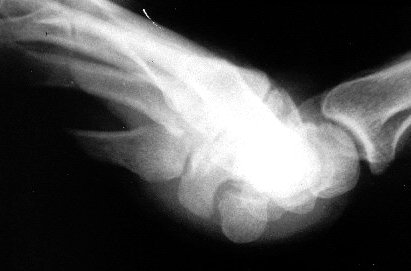

Supinated wrist- hook/pisiform Xray view